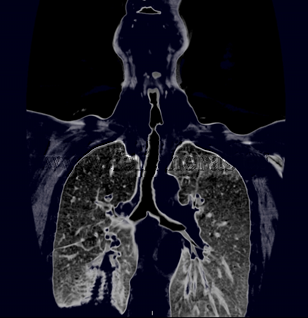

Estenosis traqueal post traqueotomía